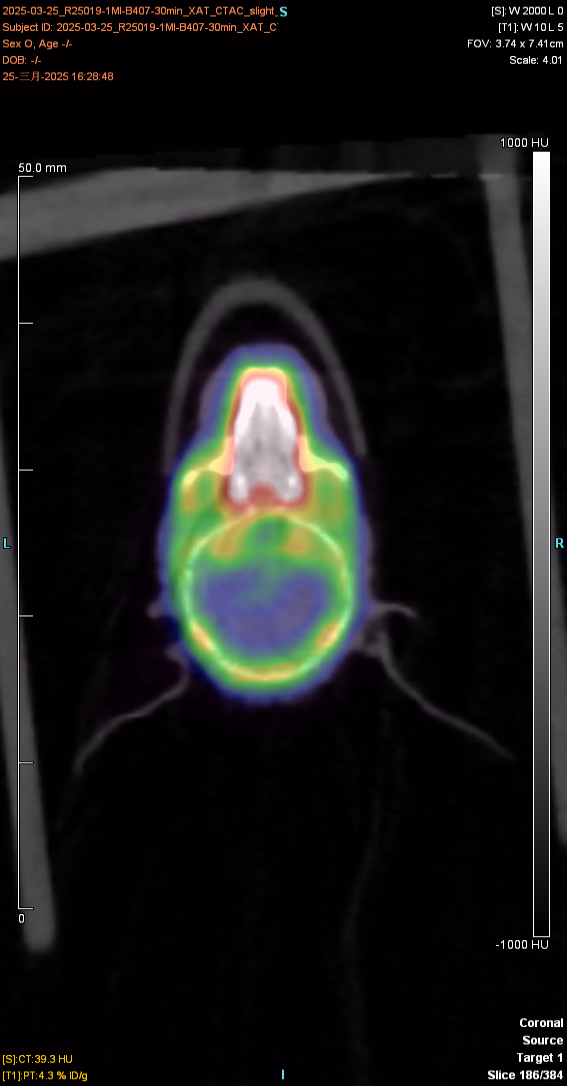

下(xià)圖為(wèi)30min顯像圖像